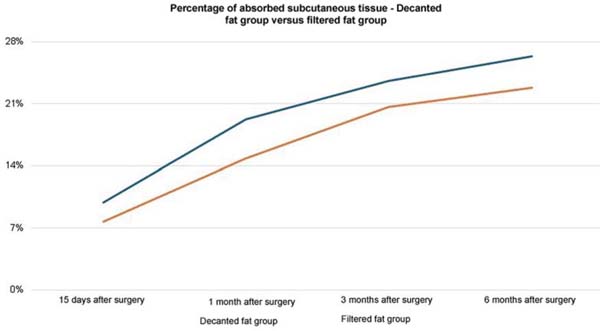

In the decanted graft group, the average reduction compared with the initial thickness after lipofilling was 9.90% on day 15, 19.27% on month 1, 23.59% on month 3, and 26.36% on month 6. In the filtered graft group, the average reduction compared to the initial thickness after lipofilling was 7.74% on day 15, 14.85% on month 1, 20.67% on month 3, and 22.80% on month 6 (►Fig. 6). ►Figs 7–8 reveal the ultrasound change in subcutaneous tissue’s thickness before and after lipofilling. ►Figs. 9–10 show the pre-and postoperative results of one patient from each group.

The comparison of subcutaneous thickness reduction at 6 months between the graft decantation and filtration techniques showed no statistically significant difference (p ¼ 0.59).